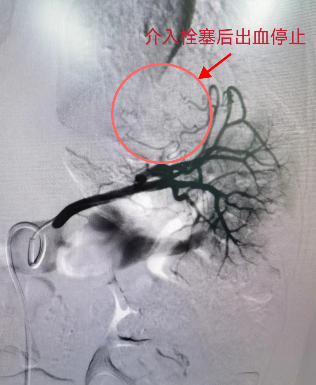

该院儿童骨病医院颉强院长团队考虑患者存在脾脏破裂活动性出血,积极联系介入诊疗中心、消化外科、重症医学科、麻醉科等多学科会诊,考虑患者年纪较小、处于生长发育阶段,经多科室MDT讨论后建议进行全麻下脾动脉栓塞术,在麻醉科及介入手术室的积极配合下,介入诊疗中心吴智群主任带领任虎虎副教授、李晨、芦军主治医师历时40分钟完成手术,术后病人转入重症监护室,24小时后复查血红蛋白98g/L,腹痛基本消失;成功挽救患者生命并且保留了患者正常的脾脏。